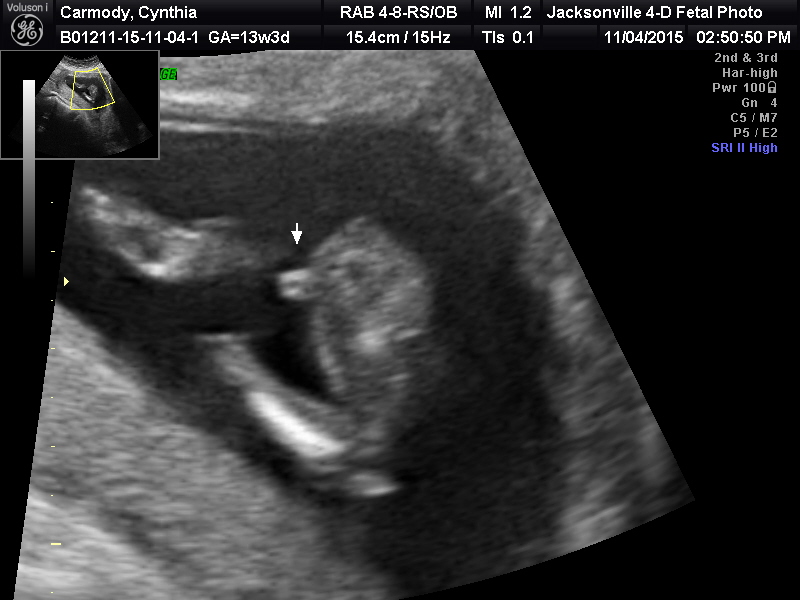

I know I accidentally posted this in the wrong section. First time using this site, I didn't know how to delete it. But can you tell the gender with the pics posted?